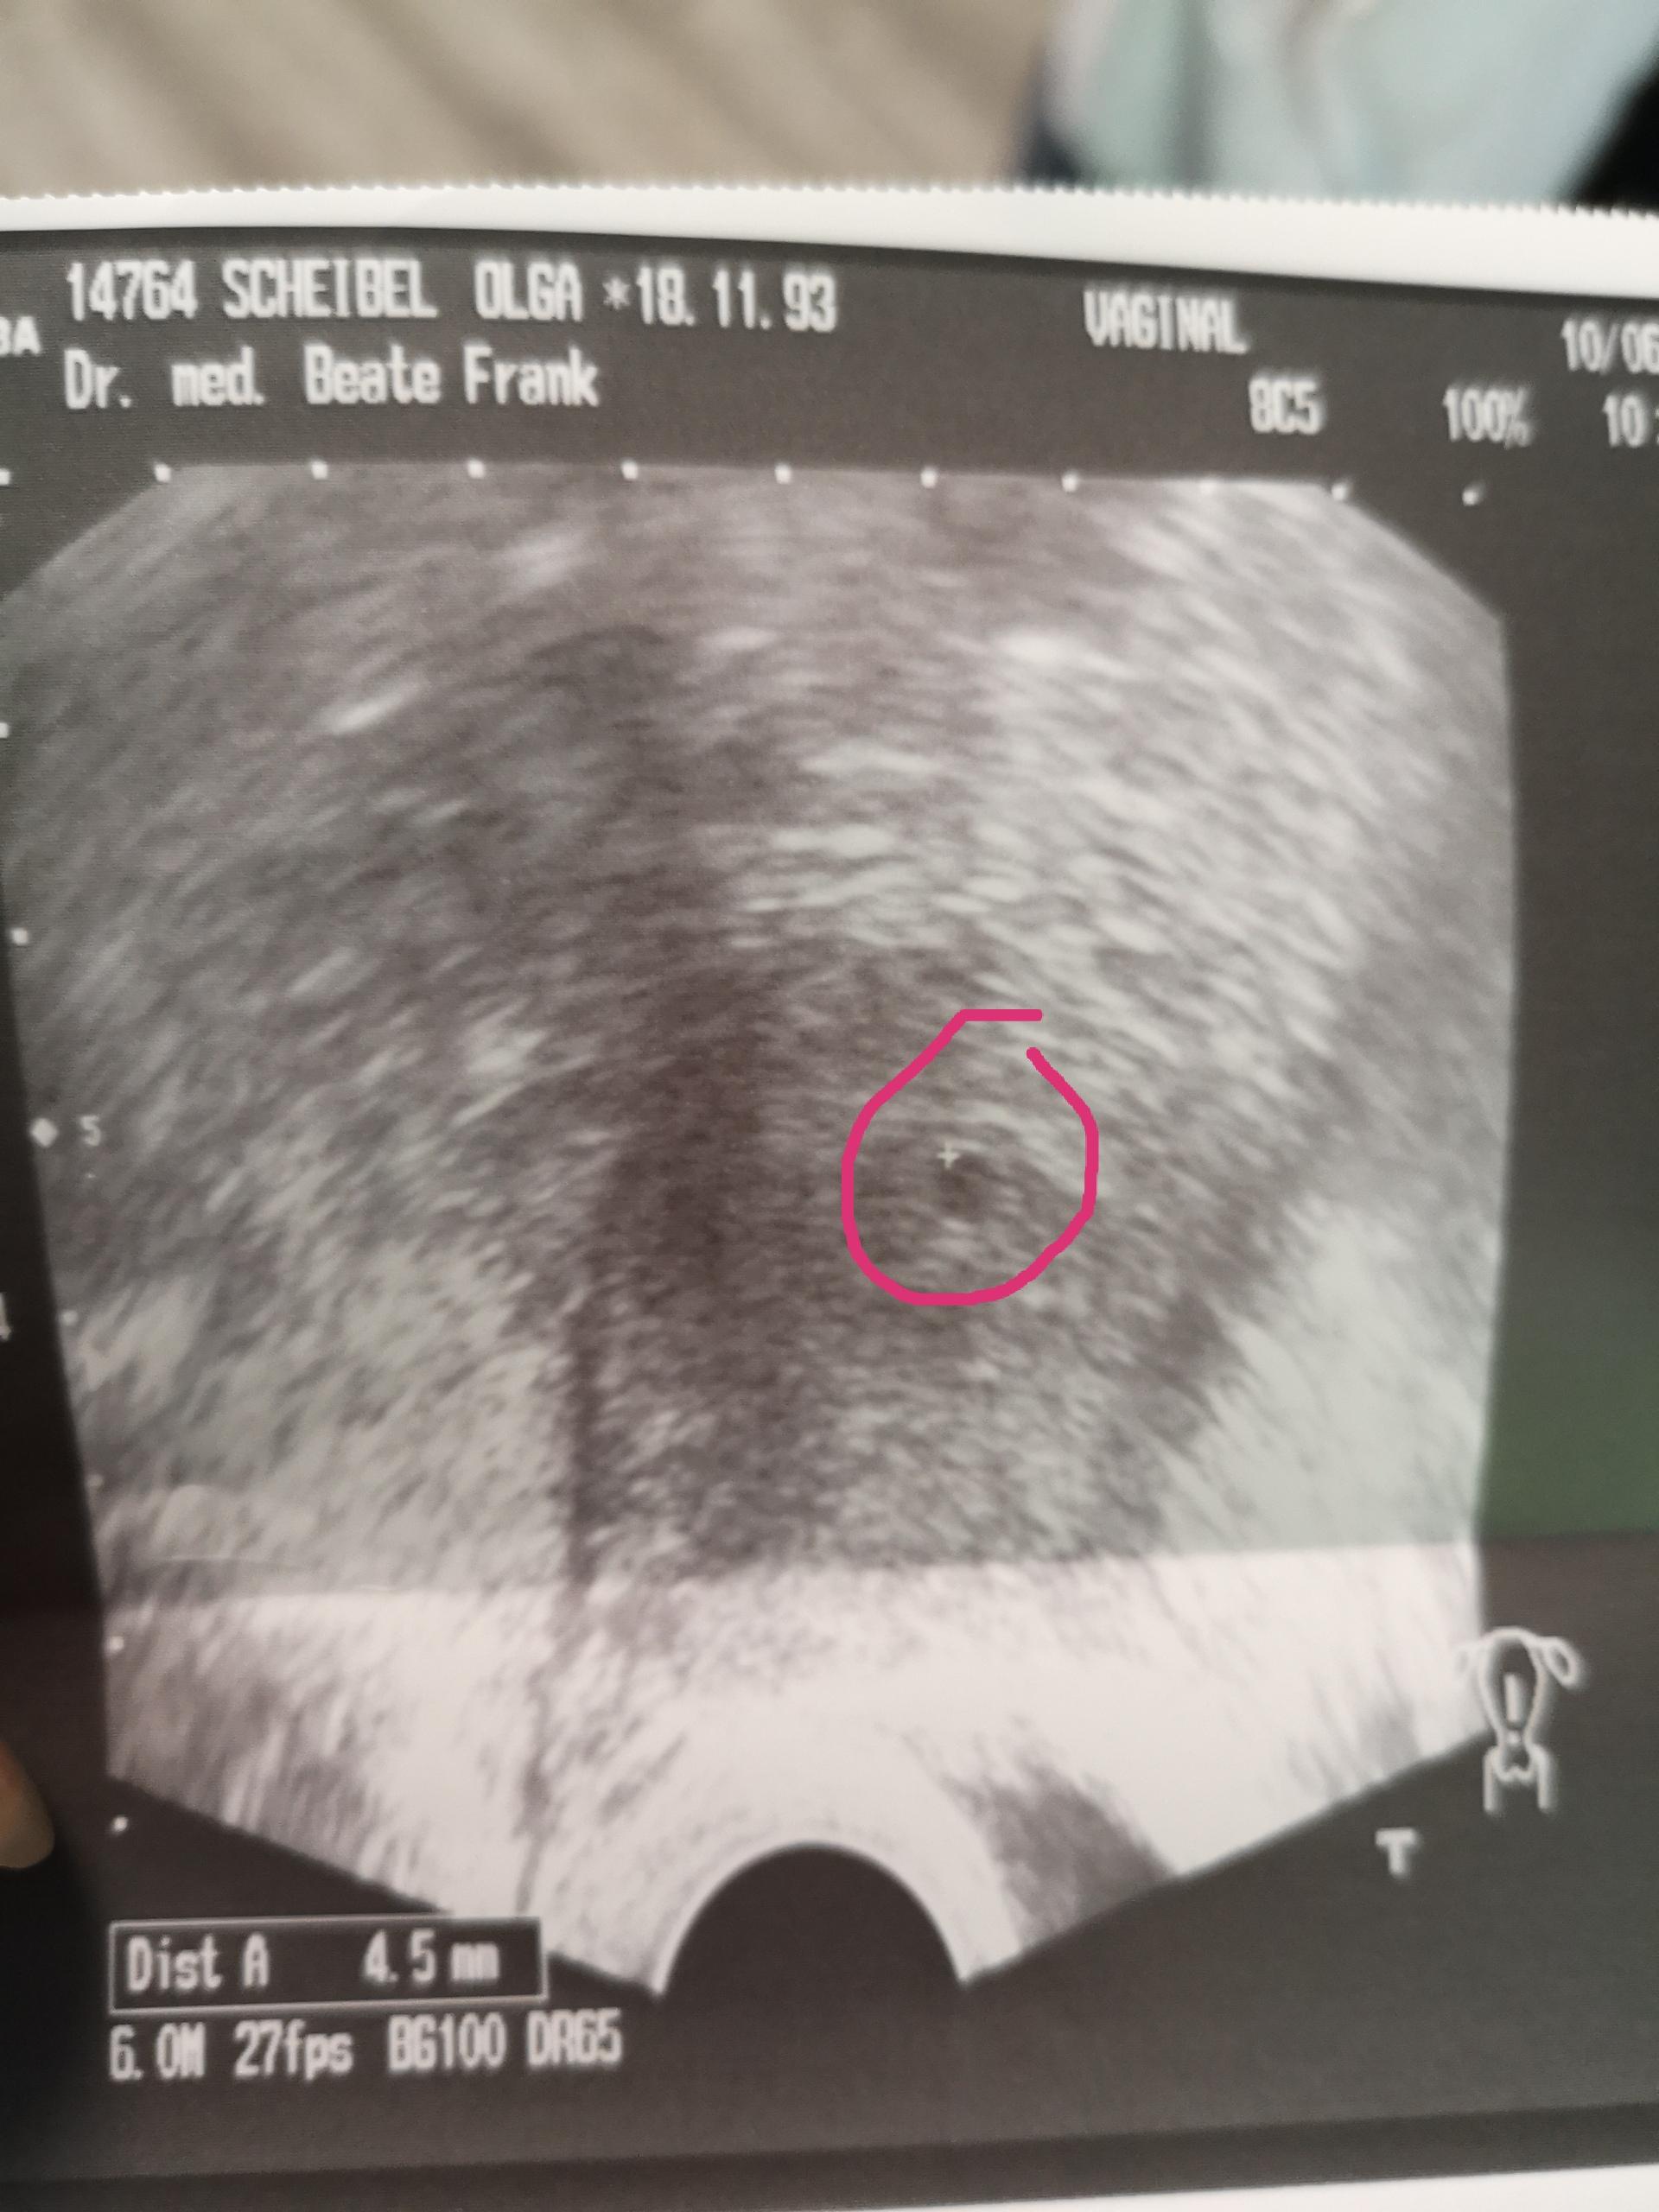

4 ssw ultraschall fruchthöhle. SSW Fruchthöhle Dottersack aber kein Embryo. Hier sieht man deutlich die schwarze Fruchthöhle der Embryo lässt sich noch nicht erkennen. Dies dient als ersten Anhaltspunkt für das Alter deiner Schwangerschaft.

Ultraschall 44 und keine fruchthöhle - wer kennt das. Keine fruchthöhle sichtbar wie groß in ssw 4 4. In Bild 1 misst die Fruchthöhle FH 5 mm.

Aber lässt sich auf dem Ultraschall in der 4. Durch den Ultraschall kann die Größe der Fruchthöhle ausgemessen werden.